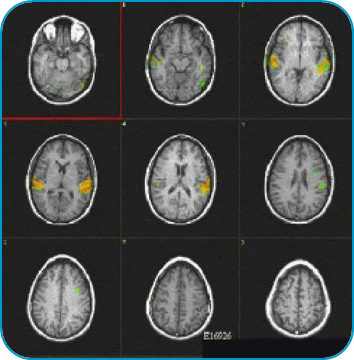

A Final Result

The areas in color depict the activation of the brain regions involved in hearing and comprehending the human voice. The left hemisphere shows greater activation.